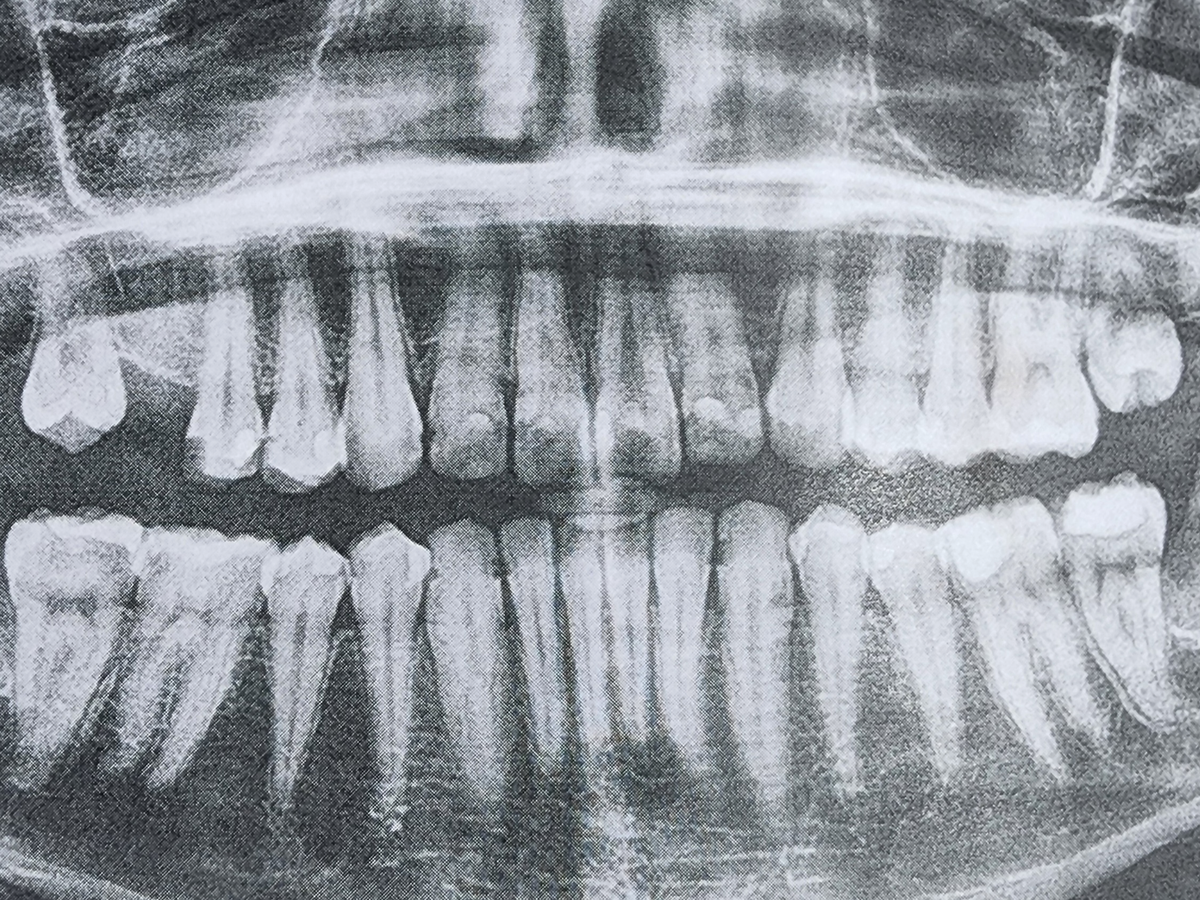

Hello. My name is Ash and those x-rays are of my not so good teeth. I knew that they weren't that good but they were worse than I could ever have imagined.

Due to an old dentist seemingly giving me bad fillings before leaving the practice, it seems I need 4 Crowns, 1 or 2 Root Canals, and a whole ton of fillings. I was prepared for a couple thousand but it seems they want about 12,400 in total. And this includes a dental plan card they let me sign up for to half the entire bill. They want me to pay before each appointment and at this point I dont know what I can do.